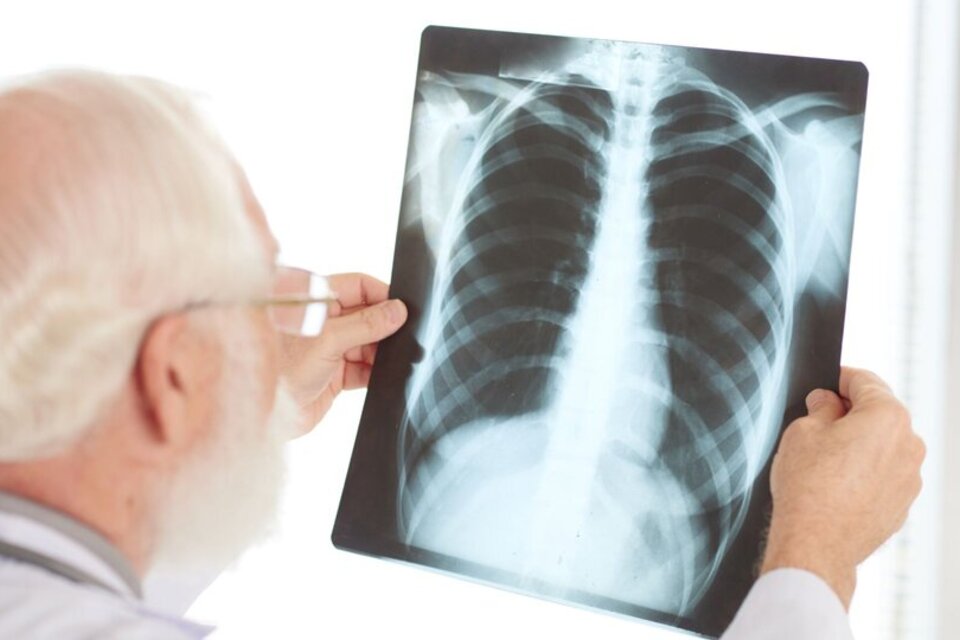

Nuemonía bilateral

En casos graves, la bacteria produce neumonía bilateral, una infección aguda del parénquima pulmonar que puede detectarse por una tomografía o radiografía de tórax.

La neumonía se desarrolla cuando los patógenos (ya sean virus, bacterias u otros microorganismos) generan inflamación e infección en los pulmones. A su vez, esa presencia de pus y líquido en los alveolos, produce una insuficiencia respiratoria grave.

La neumonía bilateral puede generar un abanico de complicaciones respiratorias, incluso puede afectar la tensión arterial o generar un absceso, o cualquier otra lesión pulmonar. Generalmente, se trata con antibióticos en los casos de una neumonía bacteriana, o bien con tratamientos que ataquen directamente los síntomas, jarabes para la tos, antifebriles, analgésicos, etcétera. En los casos de mayor gravedad, se requiere internación para inducir al paciente a una asistencia respiratoria.